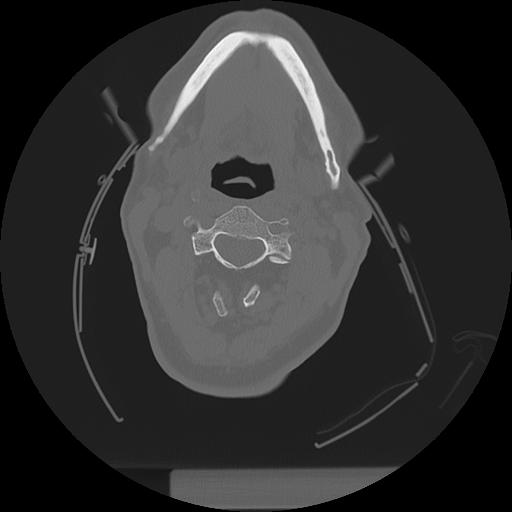

11 HUESO,,Axial,2.0,HUESO,,